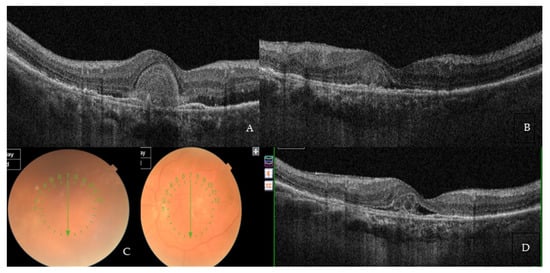

Only one 78-year-old treatment-naïve male with no previous history of systemic inflammatory diseases experienced an acute onset of anterior and intermediate uveitis, which occurred about 15 days after the second loading phase injection. The patient presented with diffuse inflammatory cells and flare within the anterior chamber and keratic endothelial precipitates, along with a significant vitreous haze. His BCVA prior to this event was 0.44 LogMar, which sharply dropped to 1.00 LogMar secondary to the uveitis. The patient was promptly started on a treatment regimen with high doses of topical and systemic steroids and mydriatic eye drops, achieving a significant improvement in the entire clinical picture after only 20 days from the start of therapy (Figure 4A–D). Eventually, the patient fully recovered, as confirmed by the full restoration of BCVA to 0.44 LogMar and the complete disappearance of any overmentioned uveitic clinical feature. Brolucizumab injections were continued as per protocol, and a strict observation was agreed with the patient, who did not show any recurrence or new onset of inflammatory adverse events.

Figure 4. Adverse event of anterior and intermediate uveitis in a 78-year-old treatment-naïve patient. (A) Baseline SD-OCT scan acquired with Maestro 3D OCT-1 (Topcon Corporation, Tokyo Japan) prior to the therapy with Brolucizumab displaying hyper-iso-reflective subretinal material distorting the retinal profile, RPE irregularities, and both IR and SR edema. BCVA at this stage was 1.00 LogMAR. (B) SD-OCT at the end of the loading phase showed a striking retinal profile restoration with an important reduction in the hyper-iso-reflective subretinal material and both the IR and SR edema. BCVA significantly improved to 0.44 LogMAR. (C) Two weeks after the second injection, an anterior and intermediate uveitis with massive vitreous haze occurred with difficulty in exploring the ocular fundus. Diffuse inflammatory cells and flare within the anterior chamber, and keratic endothelial precipitates, were also noted. BCVA dramatically dropped to 1.0 LogMAR. (D) Three weeks after therapy with high doses of topical and systemic steroids and mydriatic eye drops, a significant improvement in the entire clinical picture was achieved. Eventually, the uveitis totally resolved with a full restoration of BCVA back to 0.44 LogMAR and the complete disappearance of any uveitis clinical finding.